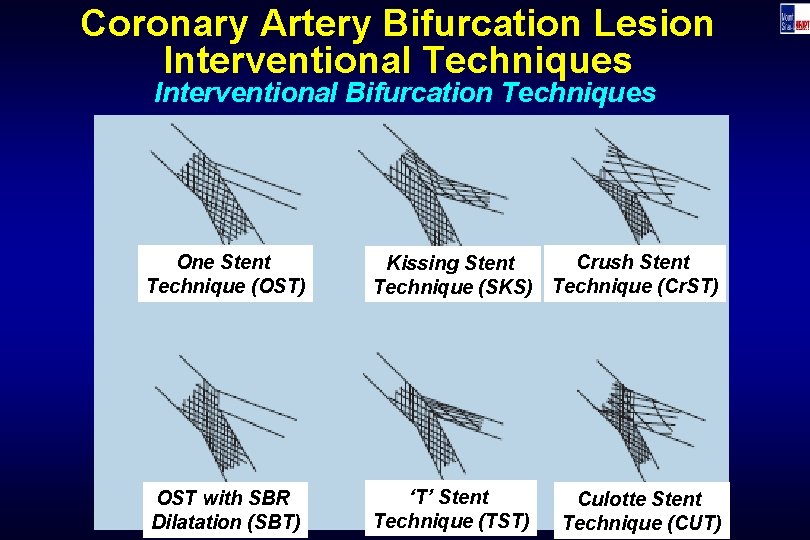

Coronary Artery Bifurcation Lesion Interventional Techniques Interventional Bifurcation Techniques One Stent Technique (OST) Crush Stent Kissing Stent Technique (SKS) Technique (Cr. ST) OST with SBR Dilatation (SBT) ‘T’ Stent Technique (TST) Culotte Stent Technique (CUT)